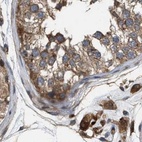

Immunohistochemical staining of human colon, kidney, liver and testis using Anti-GCC1 antibody HPA021323 (A) shows similar protein distribution across tissues to independent antibody HPA019369 (B).